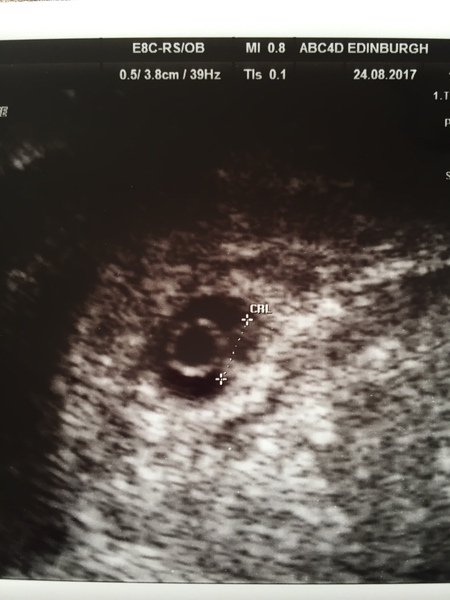

Poppyandpeaches · 26/08/2017 07:43

Here's mine. 6 weeks on the dot. Absolutely tiny but very clear heartbeat! :)